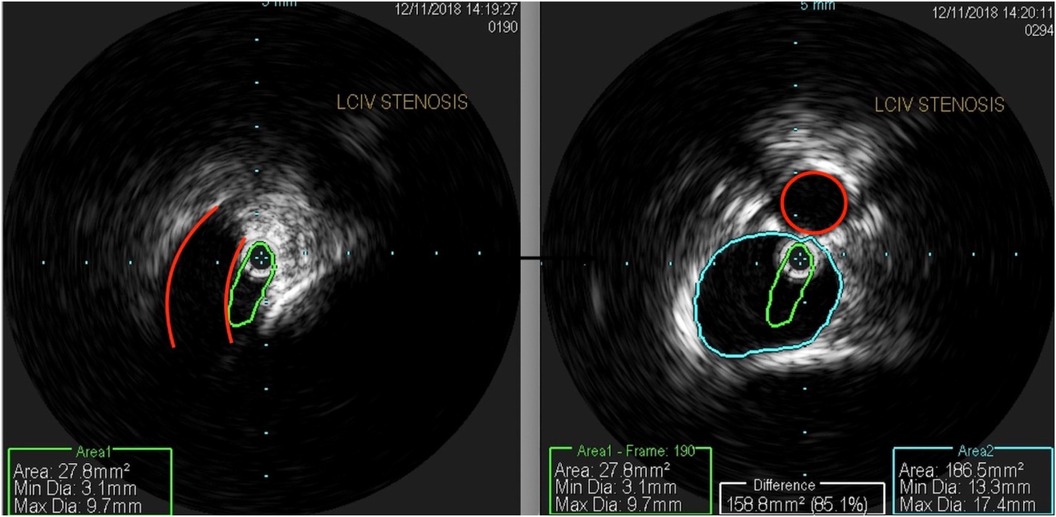

The patient underwent treatment at AMITA Hinsdale Hospital (Hinsdale, IL, USA). Under moderate sedation, the patient underwent traditional transcatheter venography (Figure 2). This, along with intravascular ultrasound (IVUS), confirmed significant (25) left common iliac vein stenosis by an overlying common iliac artery of greater than 50% (25) (Figure 3). She was initially treated with placement of a left iliac vein stent. Post procedure, she was prescribed clopidogrel for 30 days. 30–40 mm Hg waist-high compression hose were ordered, and she was advised to hydrate daily with 100 oz of electrolyte drinks. She underwent a routine clinical and imaging follow-up at 1 and 6 months. Confusion and dizzy spells were reported as alleviated at 1 month, but still some diminished cognitive clarity persisted. At 6 months, she reported improvement in cognition to a point where she reenrolled in graduate studies and resumed driving. According to her neurologist, she was having significantly fewer headaches and fatigue was reported to be reduced. Slight dizziness persisted, and she was started on a short course of midodrine. Dyspareunia persisted. She was subsequently administered a percutaneous ultrasound-guided injection of the vaginal wall and vulvar varices with 0.5% sotradecol foam using the Tessari technique (13). There were no immediate procedural complications, and her dyspareunia resolved after 3 months. At 12 months after iliac vein stenting, repeat neuropsychiatric testing (with the same examiner) showed her memory at the 95th percentile. Her full-scale IQ increased modestly. The Beck Depression Inventory II score moved to the normal range. The overall impression was “normal exam” (Supplementary Table 1). At 18 months after stenting, her dizziness returned, and dyspareunia reappeared. An ultrasound suggested a developing right iliac vein stenosis. Subsequently, a CT venogram showed the left stent pressing upon an already partially compressed right common iliac vein (Figure 4). She then underwent placement of a right-sided iliac vein stent. She was again prescribed clopidogrel, but for only 3 months, and again advised to drink 100 oz electrolyte solution daily and wear waist-high compression hose.

Figure 3

Medical imaging showing a comparison of LCIV stenosis. The left image depicts stenosis with highlighted measurements: an area of 27.8 square millimeters, a minimum diameter of 3.1 millimeters, and a maximum diameter of 9.7 millimeters. The right image shows the post-treatment state with increased measurements: an area of 186.5 square millimeters, a minimum diameter of 13.3 millimeters, and a maximum diameter of 17.4 millimeters. A red circle and color-coded outlines indicate areas of interest and measurement.

Figure 3. An intravascular ultrasound shows (left) a profile of a compressed left common iliac vein (green) by an overlying right common iliac artery (red). The right-sided image shows a composite of the normal portion of the left common iliac vein (blue) and a compressed central left common iliac vein (green), representing 85% area stenosis. The right common iliac artery is outlined in red.